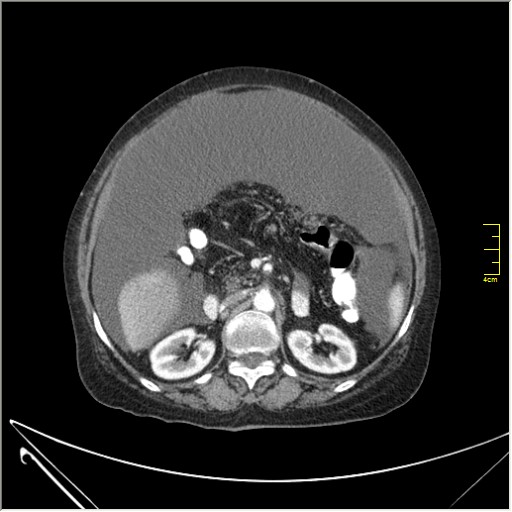

Женщина 72 года. Поступила с жалобами на вздутие живота. После осмотра хирургом, была сразу направлена на КТ брюшной полости.

Итак, асцит с объёмным образованием таза. В данном случае можно быть более конкретным, у пациентки неоплазия правого яичника с региональной лимфаденопатией (увидели?) и выраженным асцитом, характерным именно для злокачественных опухолей яичников. Пациентка оперирована ( операция Вертгейма); диагноз верифицирован: аденокарцинома правого яичника (серозная). Направлена к онкологу для дальнейшего лечения.